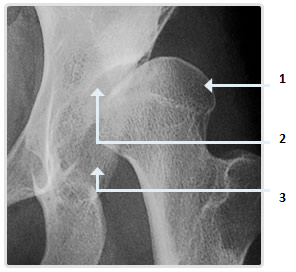

Hình 9. Bệnh nhân bị bệnh Perthes;

1.Chỏm xương đùi phát triển không bình thường.

2.Ổ chảo khớp Hông phát triển không bình thường.

3.Khớp Hông bán trận